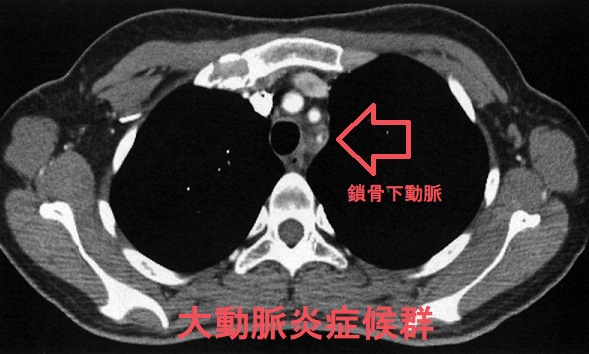

大動脈炎症候群(高安動脈炎、脈なし病)の画像所見は、

- 非造影CT;肥厚した動脈壁が高吸収

- 造影CT;

肥厚した血管壁では、中心に比べて辺縁部(内膜、外側)が強く造影される(double ring enhancement)

大動脈炎症候群 単純CT (東京レントゲンカンファレンス)